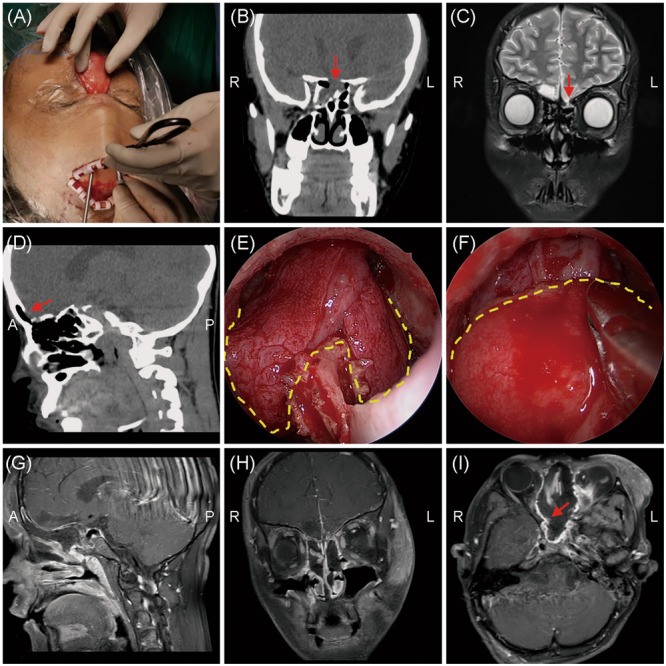

Results: A total of 94 patients with traumatic and 49 patients with nontraumatic CSF rhinorrhea were included. The prevalence of meningitis was significantly higher in traumatic CSF rhinorrhea patients (p = 0.012). Multifocal defects were more frequent in the traumatic group, while sphenoidal defects were significantly correlated with nontraumatic CSF rhinorrhea. Frontal defects were commonly identified in CSF rhinorrhea patients with meningitis than in those without, though no statistical significance was reported. Multivariate logistic regression revealed that male sex, iatrogenic traumatic CSF leak, and pneumonitis are independent factors for development of meningitis. An endoscopic approach combined with an external incision was performed in one patient and 24 patients in nontraumatic and traumatic groups, respectively (p = 0.001). Combined vascularized grafts were more commonly used in patients with traumatic CSF rhinorrhea (p < 0.05). No statistical difference in the success rate (100% vs. 97.9%) was documented between the two groups.

Conclusions: Multifocal defects and meningitis were more prevalent in traumatic CSF rhinorrhea patients, leading to increased complexity in treatment management. Iatrogenic rather than accidental traumatic CSF rhinorrhea is an independent risk factor for development of meningitis. The endoscopic combined coronal extradural approach, in conjunction with various vascularized flaps, can effectively supplement skull base reconstruction, especially for complex traumatic CSF rhinorrhea.